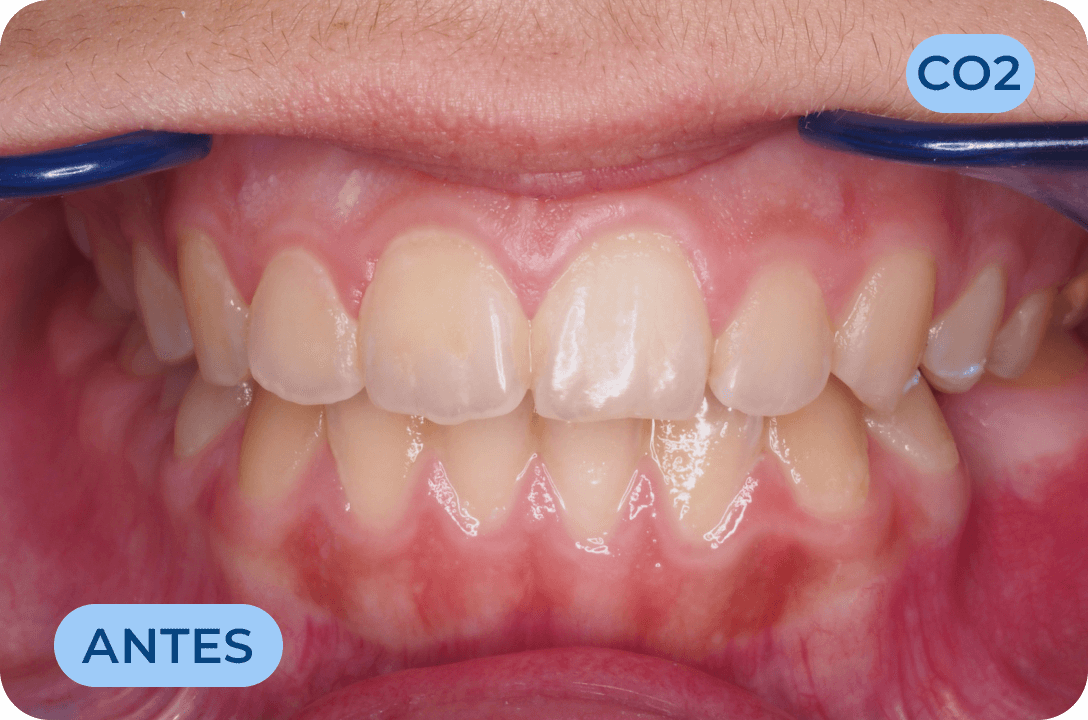

Periodontologia

Especialidade da Medicina Dentária que trata das doenças que afetam as gengivas que suportam os dentes. É responsável pelo tratamento da doença que leva à perda do maior numero de dentes em todo o mundo, a periodontite.